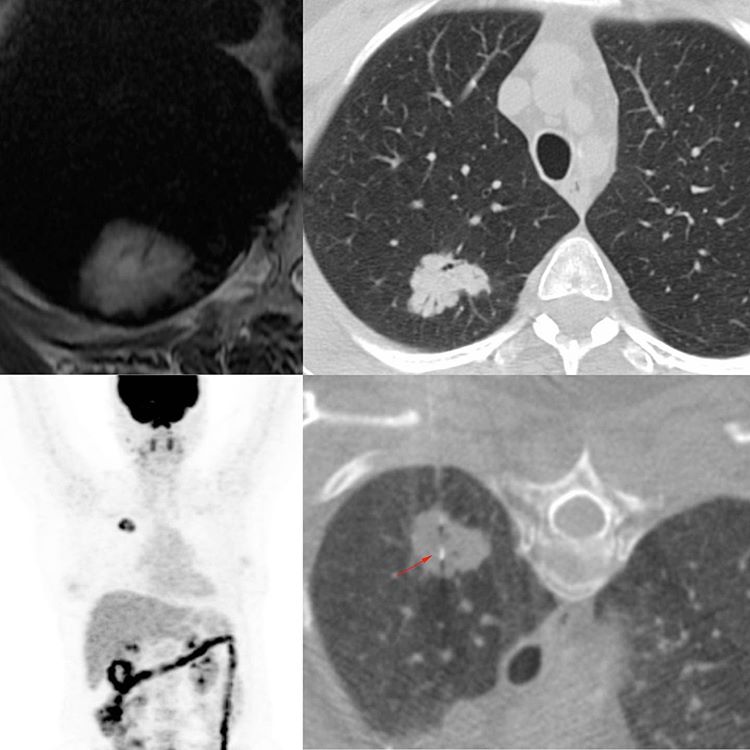

This is a 56-years old lady treated for carcinoma breast, who landed up from abroad with an MRI showing a focal lung lesion. The CT scan showed a lesion with findings that were typical of adenocarcinoma with air bronchiolograms and spiculated margins. The PET showed just this one lesion.

The question then was; is this metastasis from Ca breast or a second primary lung neoplasm.

The biopsy was easy using a 20G coaxial biopsy gun. The diagnosis was adenocarcinoma, but consistent with metastasis from Ca breast, ER +ve, PR -ve and a HER 2 NEU score of 2.